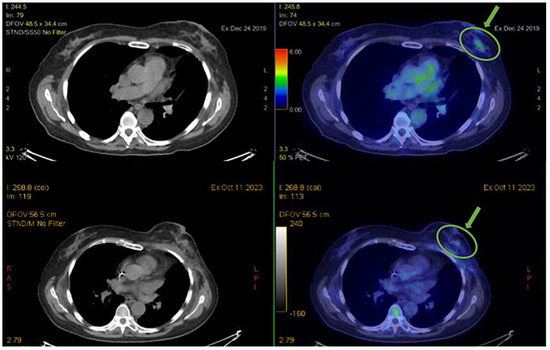

3.2.1. PET Evaluations Show Prolonged Disease Control